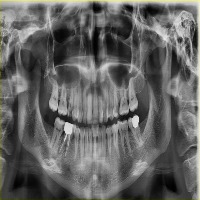

vzrad2 Computer Vision Project

Arshs Workspace Radio

downloadsClasses (93)

Amalgam filling

Bone Loss

Calculus

Caries

Cavity

Composite filling

Crown

Cyst

Implant

Periapical lesion

Root canal filling

A description for this project has not been published yet.